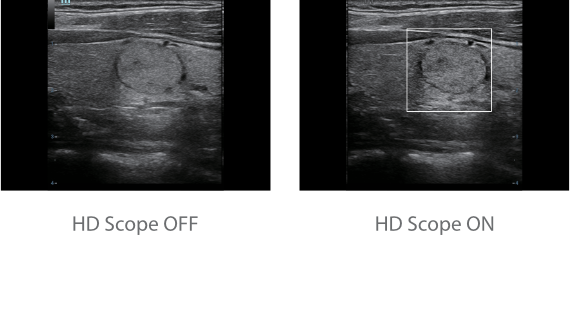

С момента основания компания Mindray непрерывно ищет новые способы повышения точности диагностики. Основанная на самой передовой технологии ZONE Sonography? новая платформа ZST+, выводит качество ультразвуковой визуализации системы Resona 7 на более высокий уровень за счет использования зонного сканирования и канальной обработки данных.

Обеспечивая качество изображения уровня премиум, Resona 7 также повышает клинические возможности исследования при помощи революционной системы V Flow, предназначенной для оценки гемодинамических показателей сосудов; обеспечивает интеллектуальное получение из 3D данных наиболее важных проекций для диагностики ЦНС плода. Сочетая в себе интуитивно понятное сенсорное управление с распознаванием жестов и все важные клинические характеристики, передовая система Resona 7 настоящая новая волна в сфере ультразвуковых инноваций.Благодаря перечисленным выше характеристикам, Resona 7 является доступным решением премиум-класса, которое удовлетворяет высоким требованиям клинической точности и эффективной диагностики в условиях современной перегруженной больничной среды.